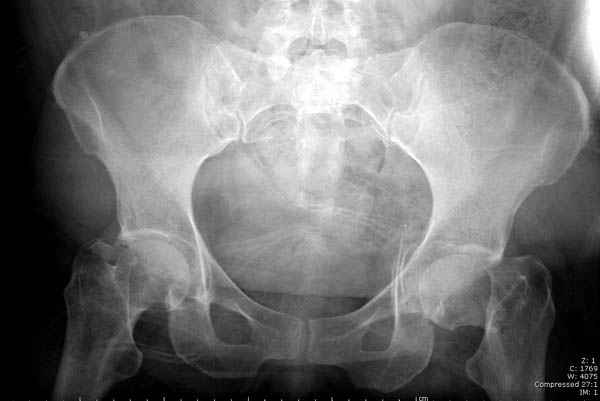

На картинке подобный случай, только без шейки, сделано через месяц или полтора после травмы.

В положении на спине подвздошным и надлобковым доступом восстанавливается тазовое кольцо, фиксация пластинами. При хорошей репозиции может улучшиться конгруэнтность в суставе.

Затем, если положение хорошее, закрытый остеосинтез шейки винтами.

Если нет - в положении на боку, синтез задней колонны из наружно-латерального доступа и синтез головки винтами, но уже под визуальным контролем.